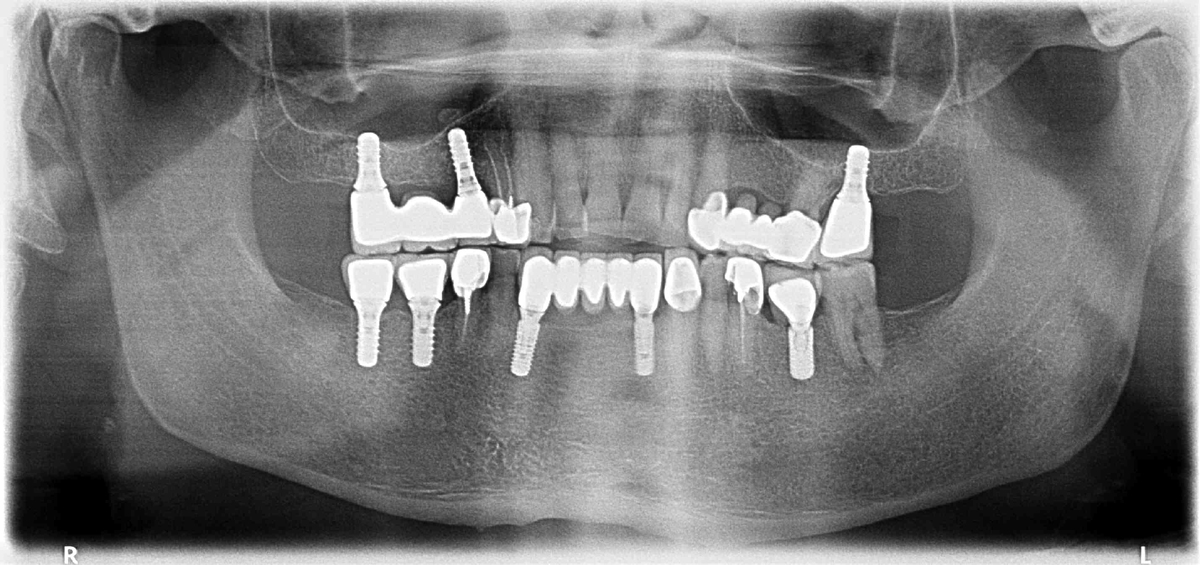

Lo studio del Dottor Vitanza si è rivelato una scelta eccellente. Un'ortopanoramica per cominciare e gran professionalità nell'analisi delle soluzioni. Grazie Dottore.

Avevo un problema che pensavo irrisolvibile invece in pochissimo tempo grazie all’innesto degli impianti eseguito dal dott. Vitanza ho ritrovato quella serenità mia sperata. Consiglio assolutamente il dott. Vitanza per la sua estrema professionalità oltre che cordialità. Lo studio è molto confortevole a davvero in ottima posizione. Tutta l'equipe merita un grande riconoscimento. Grazie ancora a presto